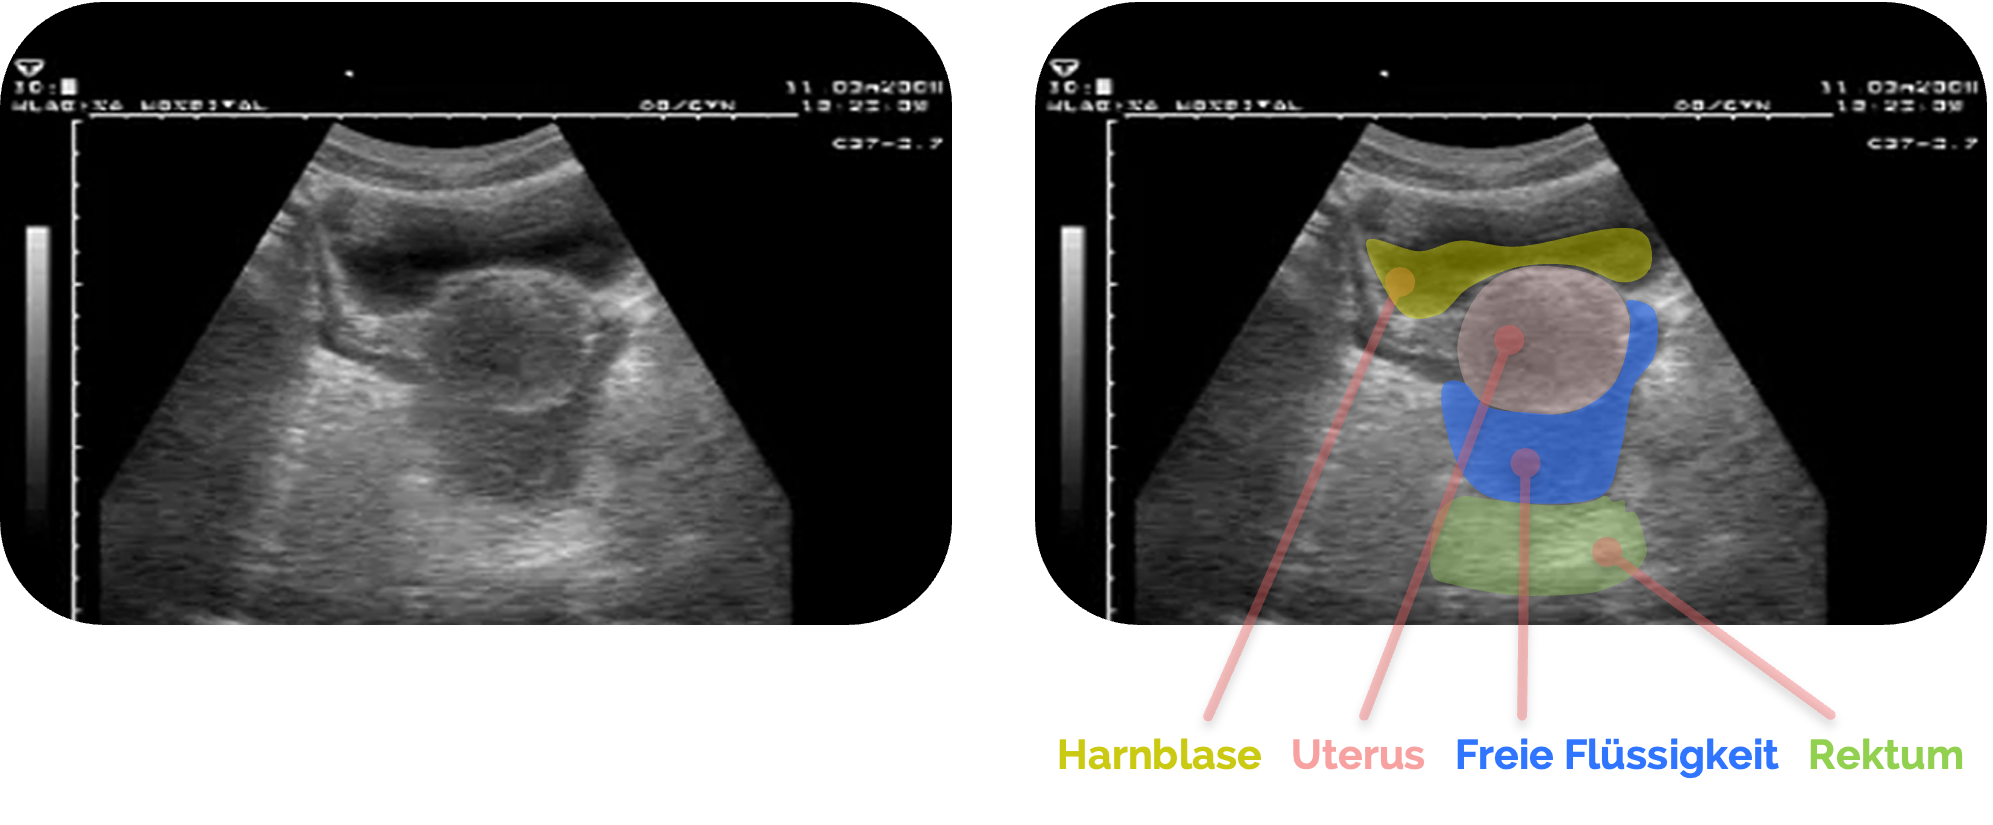

Normalbefund bei der Frau

Im Normalbefund zeigt sich der Douglas-Raum als schmaler, echoarmer Spaltraum ohne erkennbare Flüssigkeit. Der Uterus ist ventral davon klar abgegrenzt sichtbar, meist mit homogener Echostruktur des Myometriums und einer regelmäßig aufgebauten Endometriumschicht.

Das Rektum

Eine geringe Menge an freier Flüssigkeit kann beim weiblichen Zyklus

Figure 1 aus Bourcier, JE., Gallard, E., Redonnet, JP. et al. Diagnostic performance of abdominal point of care ultrasound performed by an emergency physician in acute right iliac fossa pain. Crit Ultrasound J 10, 31 (2018). https://doi.org/10.1186/s13089-018-0112-5. Es wurden die farbigen Markierungen und Beschriftungen des rechten Bildes ergänzt.

Gelegentlich können sich auch funktionelle Ovarialzysten in der Nähe des Douglas-Raums abzeichnen, die meist glatt begrenzt, rundlich und anechogen sind.

Ebenso kann die Darstellung der Uterusbewegung beim Atemzyklus helfen, den physiologischen Flüssigkeitssaum von pathologischen Ansammlungen zu unterscheiden.

Entscheidend ist die Beurteilung im Kontext des Zyklus und der Klinik: Eine geringe freie Flüssigkeitsmenge bei einer ansonsten unauffälligen Sonographie ist häufig normal, während größere oder deutlich echogene Flüssigkeitsmengen, insbesondere mit septierten Anteilen, weiter abgeklärt werden müssen.